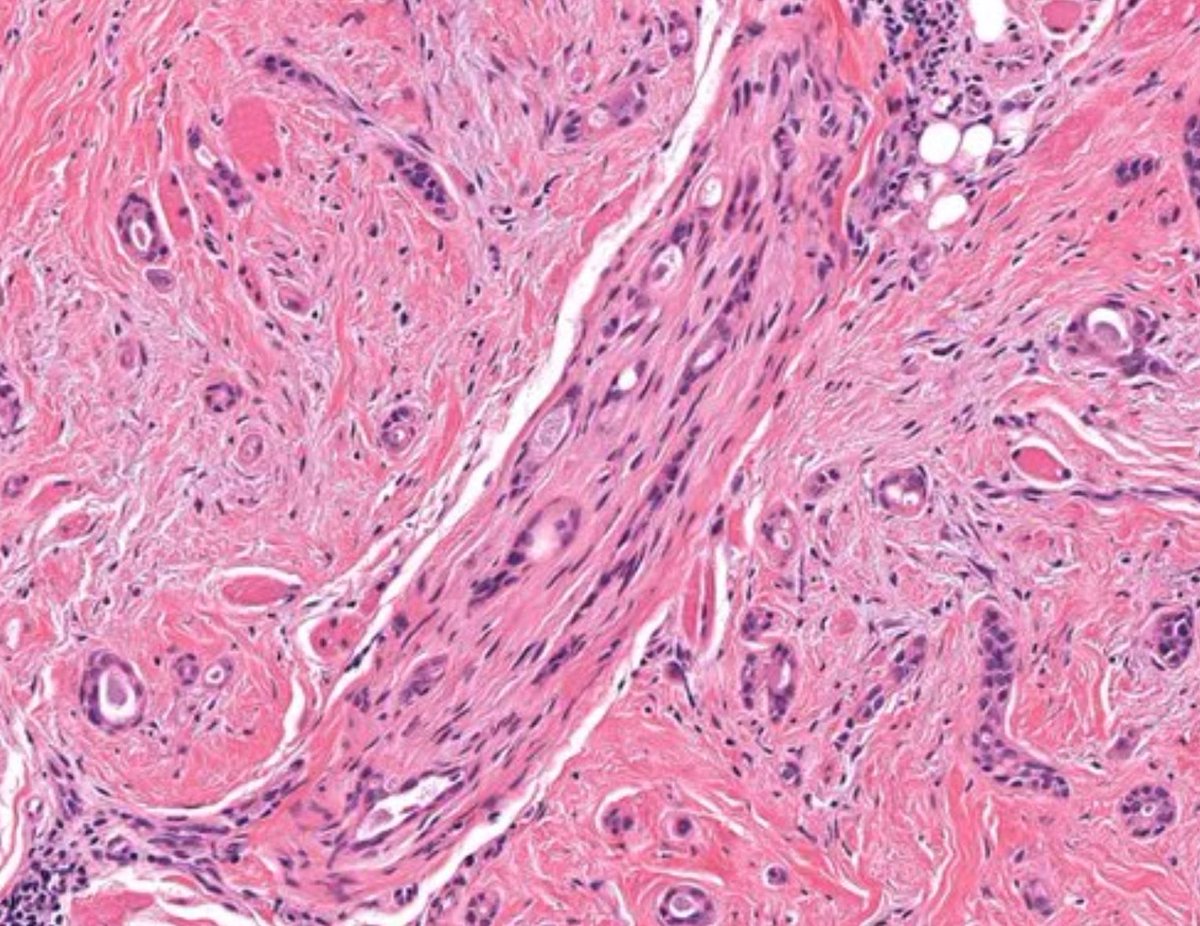

Rare (in my practice) & classic! Only case in my collection. Foot nodule 50 M. Answer ✅ youtu.be/g7PlwuIDs7U?si… Digital slide: kikoxp.com/posts/2338 Clinical pics: kikoxp.com/posts/2341 #Pathology #pathTwitter #dermpath #dermatology #dermatologia #dermtwitter

Rare (in my practice) & classic! Only case in my collection. Foot nodule 50 M.

Answer ✅ youtu.be/g7PlwuIDs7U?si…

Digital slide: kikoxp.com/posts/2338

Clinical pics: kikoxp.com/posts/2341

#Pathology #pathTwitter #dermpath #dermatology #dermatologia #dermtwitter